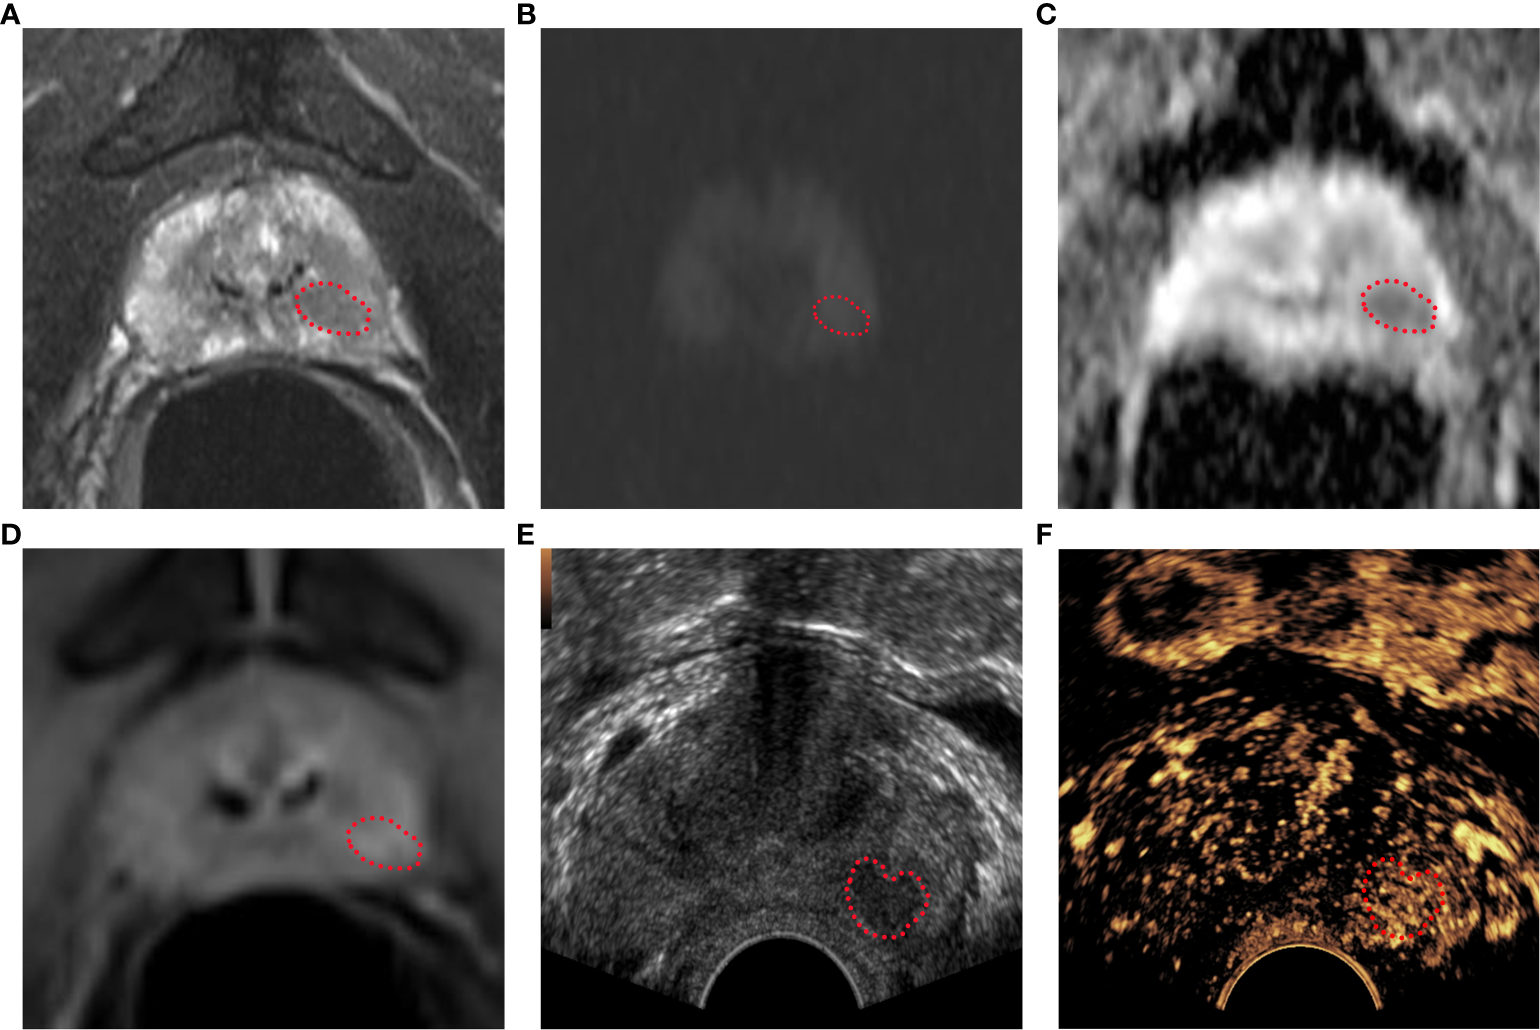

Bp-MRI score, PI-RADS v2.1 score, and CEUS-BpMRI score results display. Bp-MRI score was 3. PI-RADS v2.1 score was 4. The CEUS-BpMRI score was 4. The lesion was marked with a red dashed line. (A) T2WI score was 4. (B) DWI (B value 1000) and (C)ADC. (D) DCE: positive. (E) Conventional ultrasound. (F) CEUS: positive.

The GE Logiq E9 ultrasound diagnostic instrument (GE Healthcare, Milwaukee, WI, USA) was used. The frequency of the transrectal probe IC5-9-D was 3-9 MHz. The CE-TRUS examination was performed by two senior sonographers with 10 years of CEUS experience. On examination, the patient was in the left lateral decubitus position with both legs flexed and his knees folded with his hands. First, a conventional transrectal ultrasound was performed to observe the shape, size, and boundary between the peripheral zone and transitional zone of the prostate and whether there were nodules or abnormal blood flow signals. After real-time fusion of MRI and ultrasound images, the suspicious lesions of the prostate indicated by MRI were located, and CE-TRUS was performed on this plane. The ultrasound contrast agent (Sonovue, Bracco) suspension with a concentration of 2.4 mI was rapidly injected through the median vein of the elbow, followed by rapid flushing with 5 ml of physiological saline. The contrast-enhanced appearance of the prostate was observed for 3 minutes until the contrast agent subsided, then the data were stored in DICOM format. Time Intensity Curve (TIC) curve was drawn, and peak intensity (PI) and time to peak (TTP) were recorded. After outlining the region of interest (ROI), the TIC curve was obtained through the analysis software, as well as the quantitative analysis values of PI and TTP. The CEUS-BpMRI score was determined (Table 1, Figure 2). The conclusions were reached through discussion when differences were found.